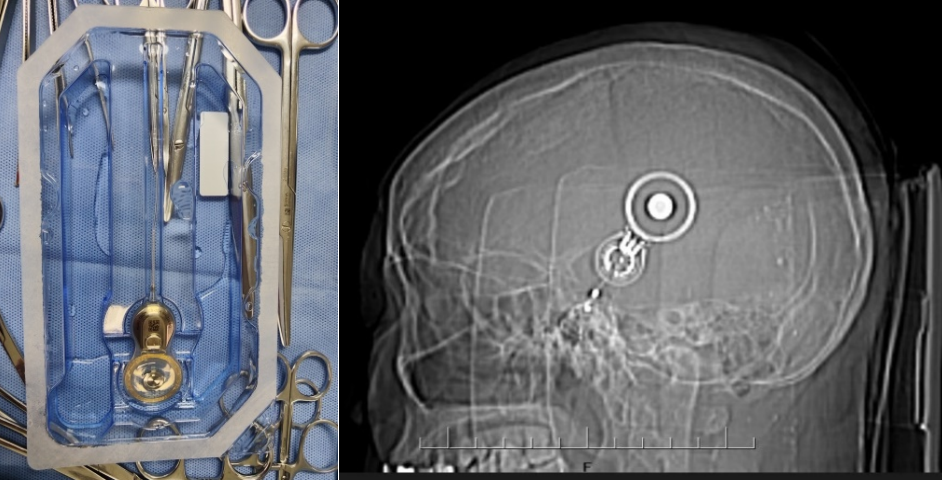

入院后,昆医大附二院耳鼻咽喉科专家团队对徐某进行了全面细致的检查和评估,结合他的具体情况,制定了个性化的手术方案。手术过程顺利,成功将集采的人工耳蜗植入徐某耳内,术中神经电生理监测,耳蜗电极均正常工作,术后耳蜗CT显示电极位置正确。术后,经过医护人员精心av线上和康复指导,徐某恢复良好,各项指标正常,顺利出院。主刀医生白忠主任叮嘱患者,1个月后返院,人工耳蜗开机后,患者就可以听到声音了,恢复有声世界。

据昆医大附二院耳鼻咽喉科专家白忠主任医师介绍,人工耳蜗是一种电子装置,通过植入体内的电极系统直接刺激听神经,帮助重度、极重度感音神经性耳聋患者恢复听力。以往,人工耳蜗价格高昂,让许多患者望而却步。此次国家集采政策落地云南后,人工耳蜗价格大幅下降,极大减轻了患者的经济负担,让更多听障患者有机会接受治疗,重获听力。